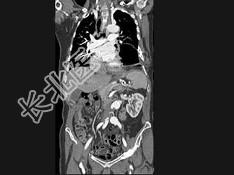

- 单项选择题男,24岁, 四肢细长,蜘蛛指, 肌张力降低,结合图像, 最可能的诊断是 ( )

C、马方综合征